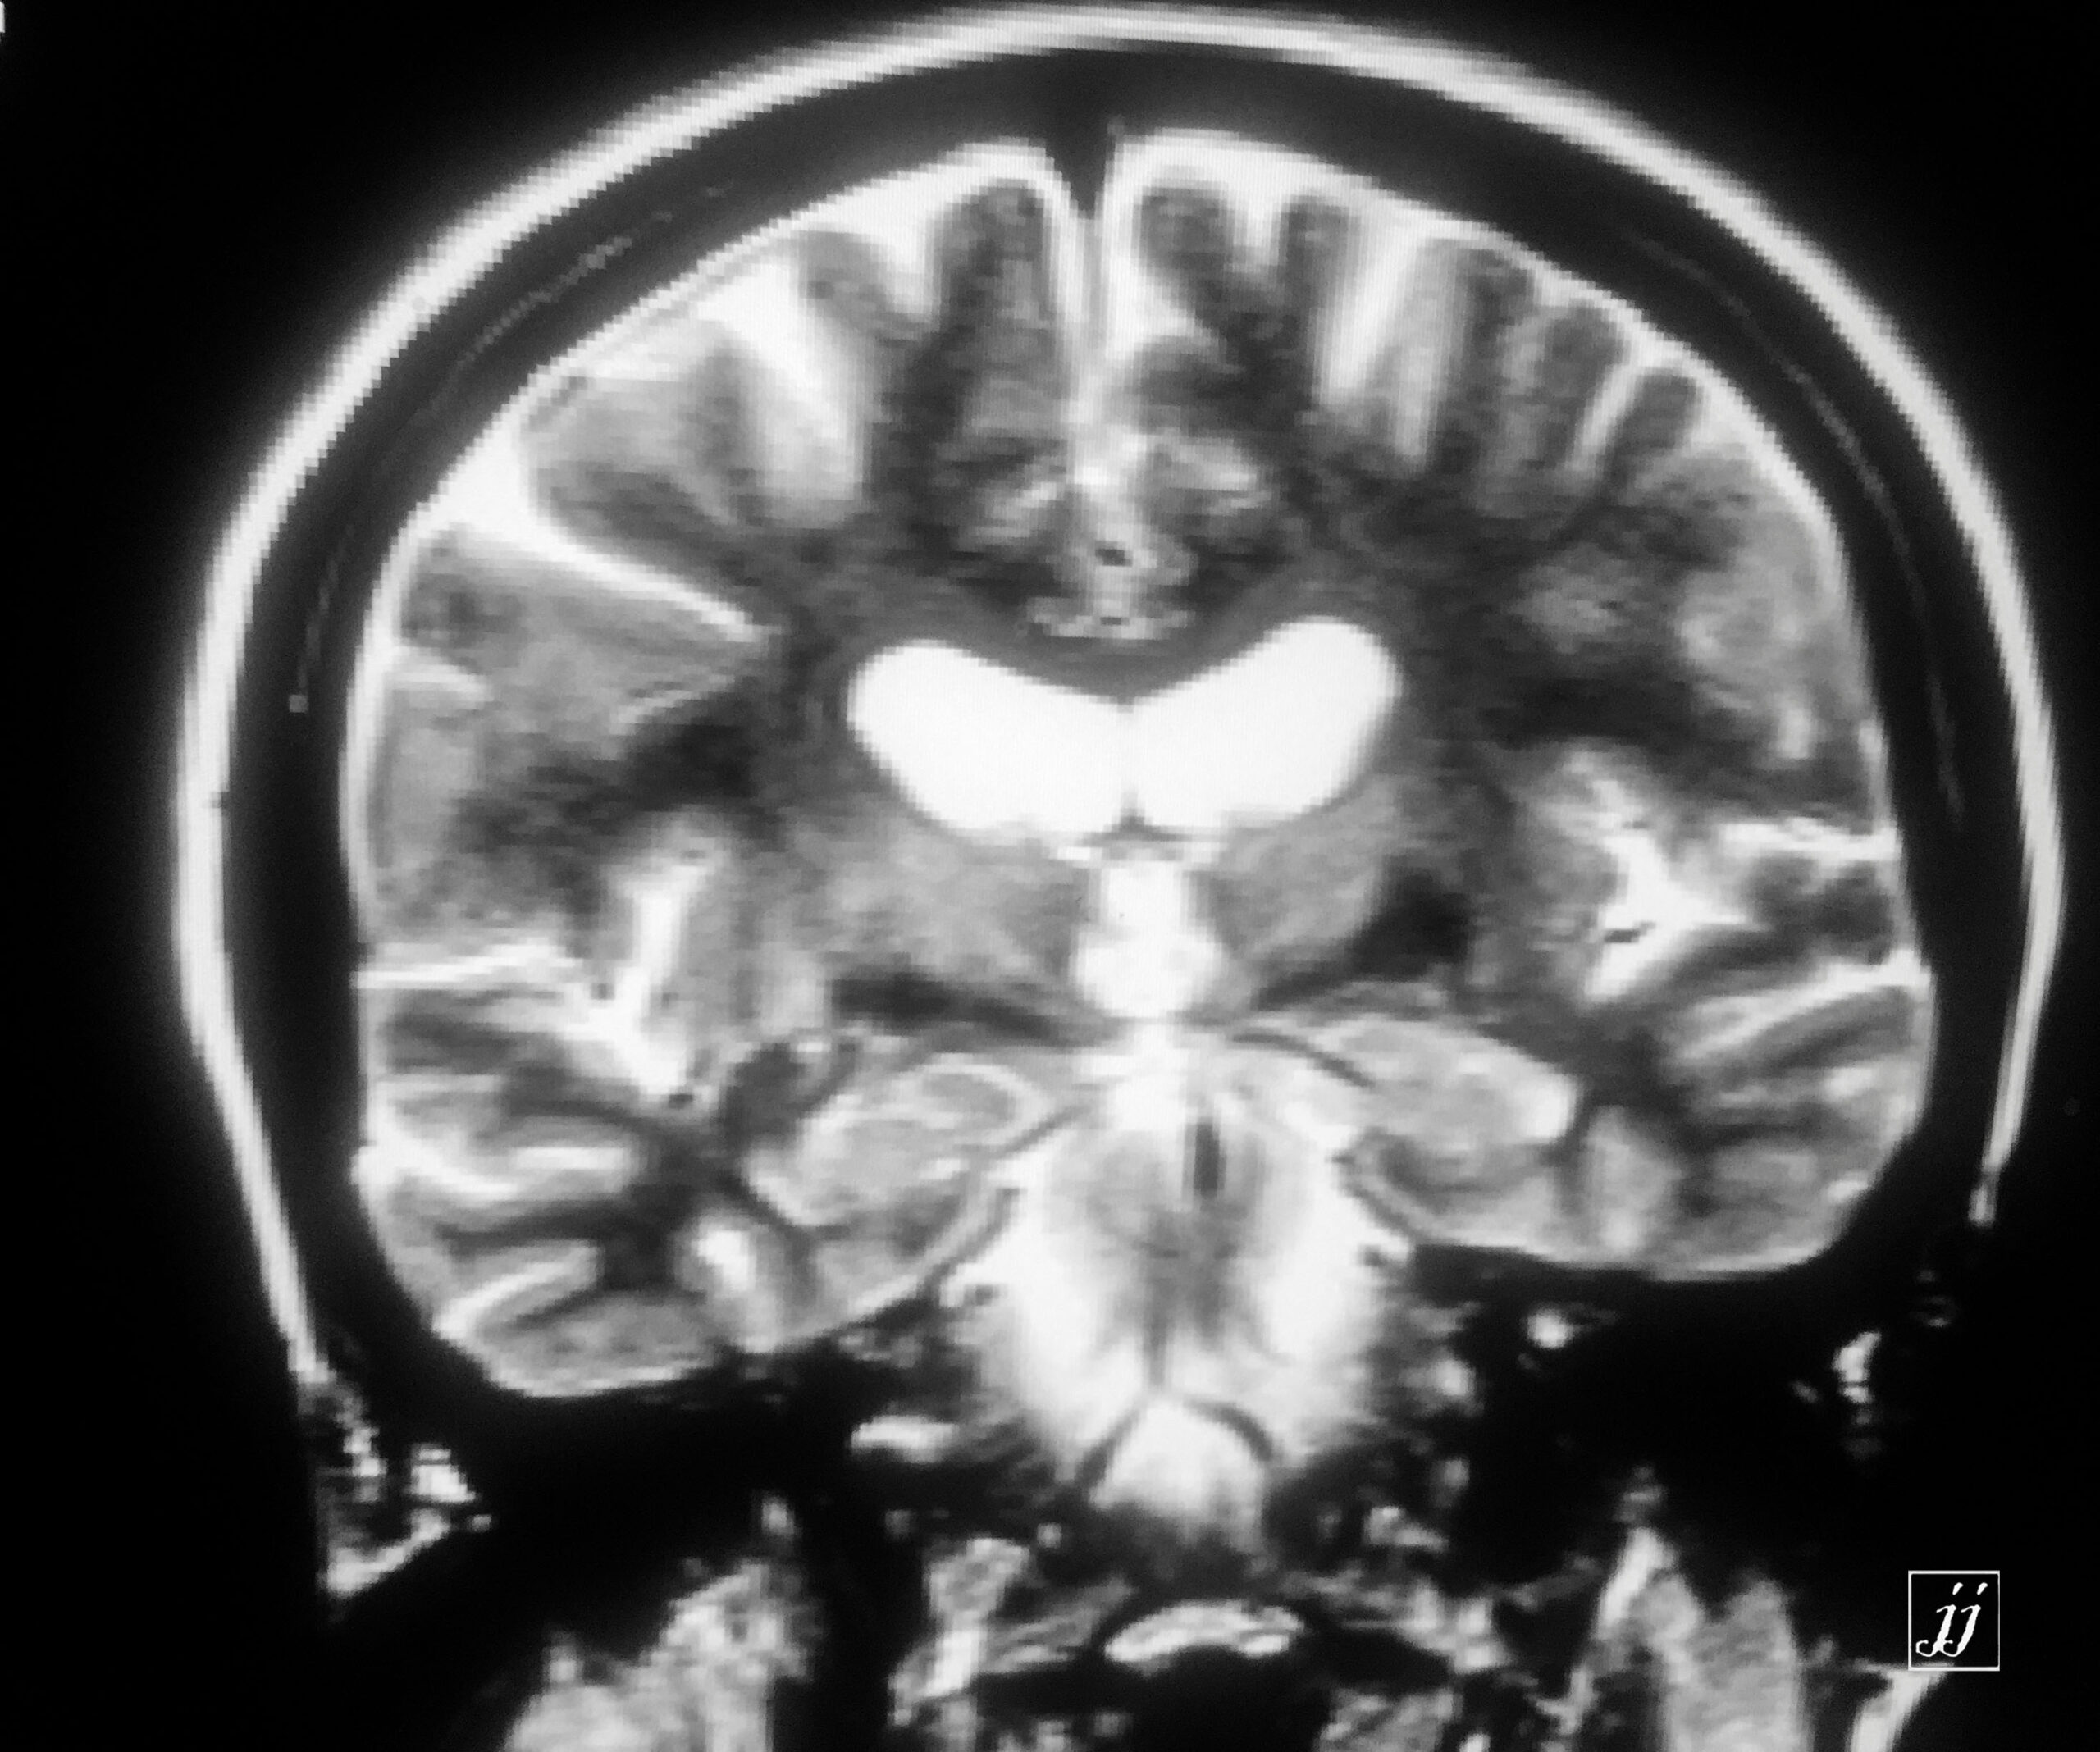

Brain- deep white mater abnormal signal degenerative type (6)